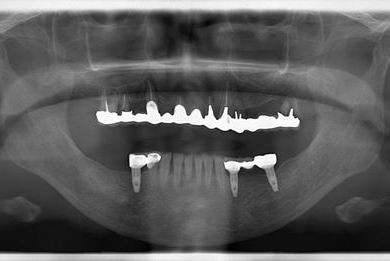

インプラントの症例写真 IMPLANT

インプラント治療+セラミック治療

| 性別/年齢 | 女性 / 59歳 | ||||||||||||||||||||||||||||||||

| 主訴 | 上の奥歯がむし歯で治したい。下の歯が少ないので、インプラントか入れ歯、できれば併用で。 | ||||||||||||||||||||||||||||||||

| 治療方針 | インプラント治療にて、機能的・審美的回復を行う。 | ||||||||||||||||||||||||||||||||

| 治療内容 | インプラント3本、ハイブリッドセラミッククラウン5本 | ||||||||||||||||||||||||||||||||

| 総治療費 | 1,116,308円 | ||||||||||||||||||||||||||||||||

| 治療期間 | 7ヶ月 |